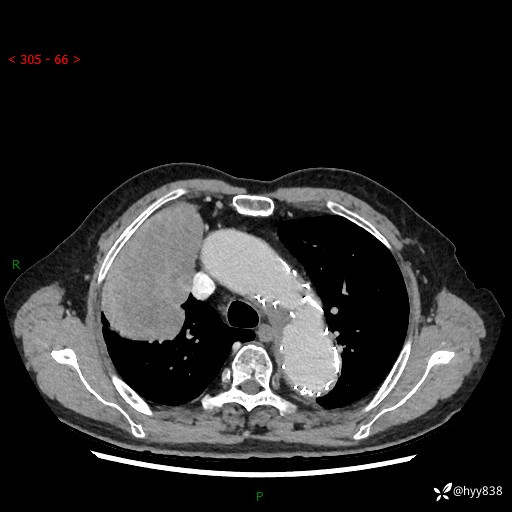

静脉期